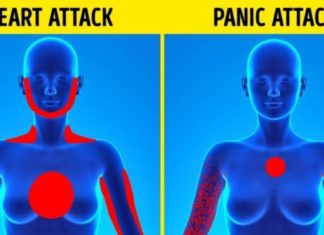

Si të bëni dallimin midis: Sulmit të panikut dhe sulmit në zemër?

Që të bëhet dallimi ndërmjet sulmit të panikut dhe sulmit në zemër mund të jetë mjaftë e vështirë, sidomos nëse personi nuk ka përjetuar simptoma të ngjashme më parë. Megjithatë, disa elemente krijojnë dallime...